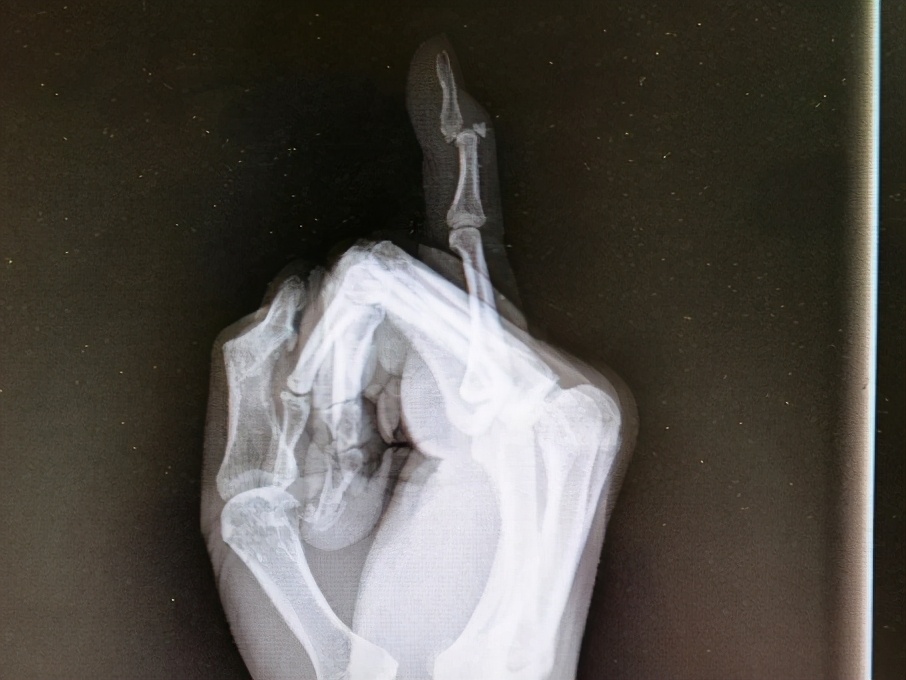

“吃萝卜干”的医学术语是“锤状指”,因为这种手指外伤畸形很像我们日常生活中用的木锤,故而取名为“锤状指”。

在一些意外情况下,手指在伸直位时,受到了突然剧烈的弯曲应力,导致背伸肌腱在止点附近处断裂,常合并止点处的撕脱骨折,从而使最后一节指骨不能伸直,并因为屈指肌腱的牵拉力而使手指末节呈屈曲状,就形成了所谓的“锤状指”。多由于打球前准备活动不足、传接球技术不正确等原因引起。

“锤状指”一旦发生,手指最后一节不能主动伸直,被动可以伸直,但弯曲不受影响,常伴患指发红肿胀。早期患指弯曲程度较轻,若未及时固定,反复活动则可造成弯曲畸形加重,后期瘢痕粘连,就会形成锤状畸形。

首先要去医院行X线检查并确诊是否有骨折,针对早期的和不伴有骨折或轻微无移位骨折的“锤状指”,优先选择保守治疗,将患指用夹板、支具或石膏固定在轻度背伸位,使得撕脱肌腱和指骨基底保持接触,固定时间约 4-6周。

对保守治疗无效,陈旧性或伴有撕脱骨折的可考虑手术治疗,一般包括微创克氏针固定、带线锚钉固定,肌腱止点重建等。